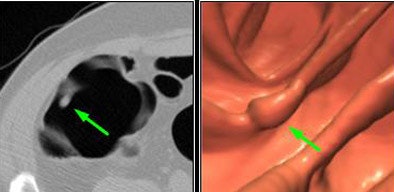

![]() |

| From Duke (Rockey et al) trial database: 10-mm pedunculated polyp in cecum missed by CTC but detected by CAD. Images courtesy of Dr. Hiroyuki Yoshida, Pickhardt et al. |